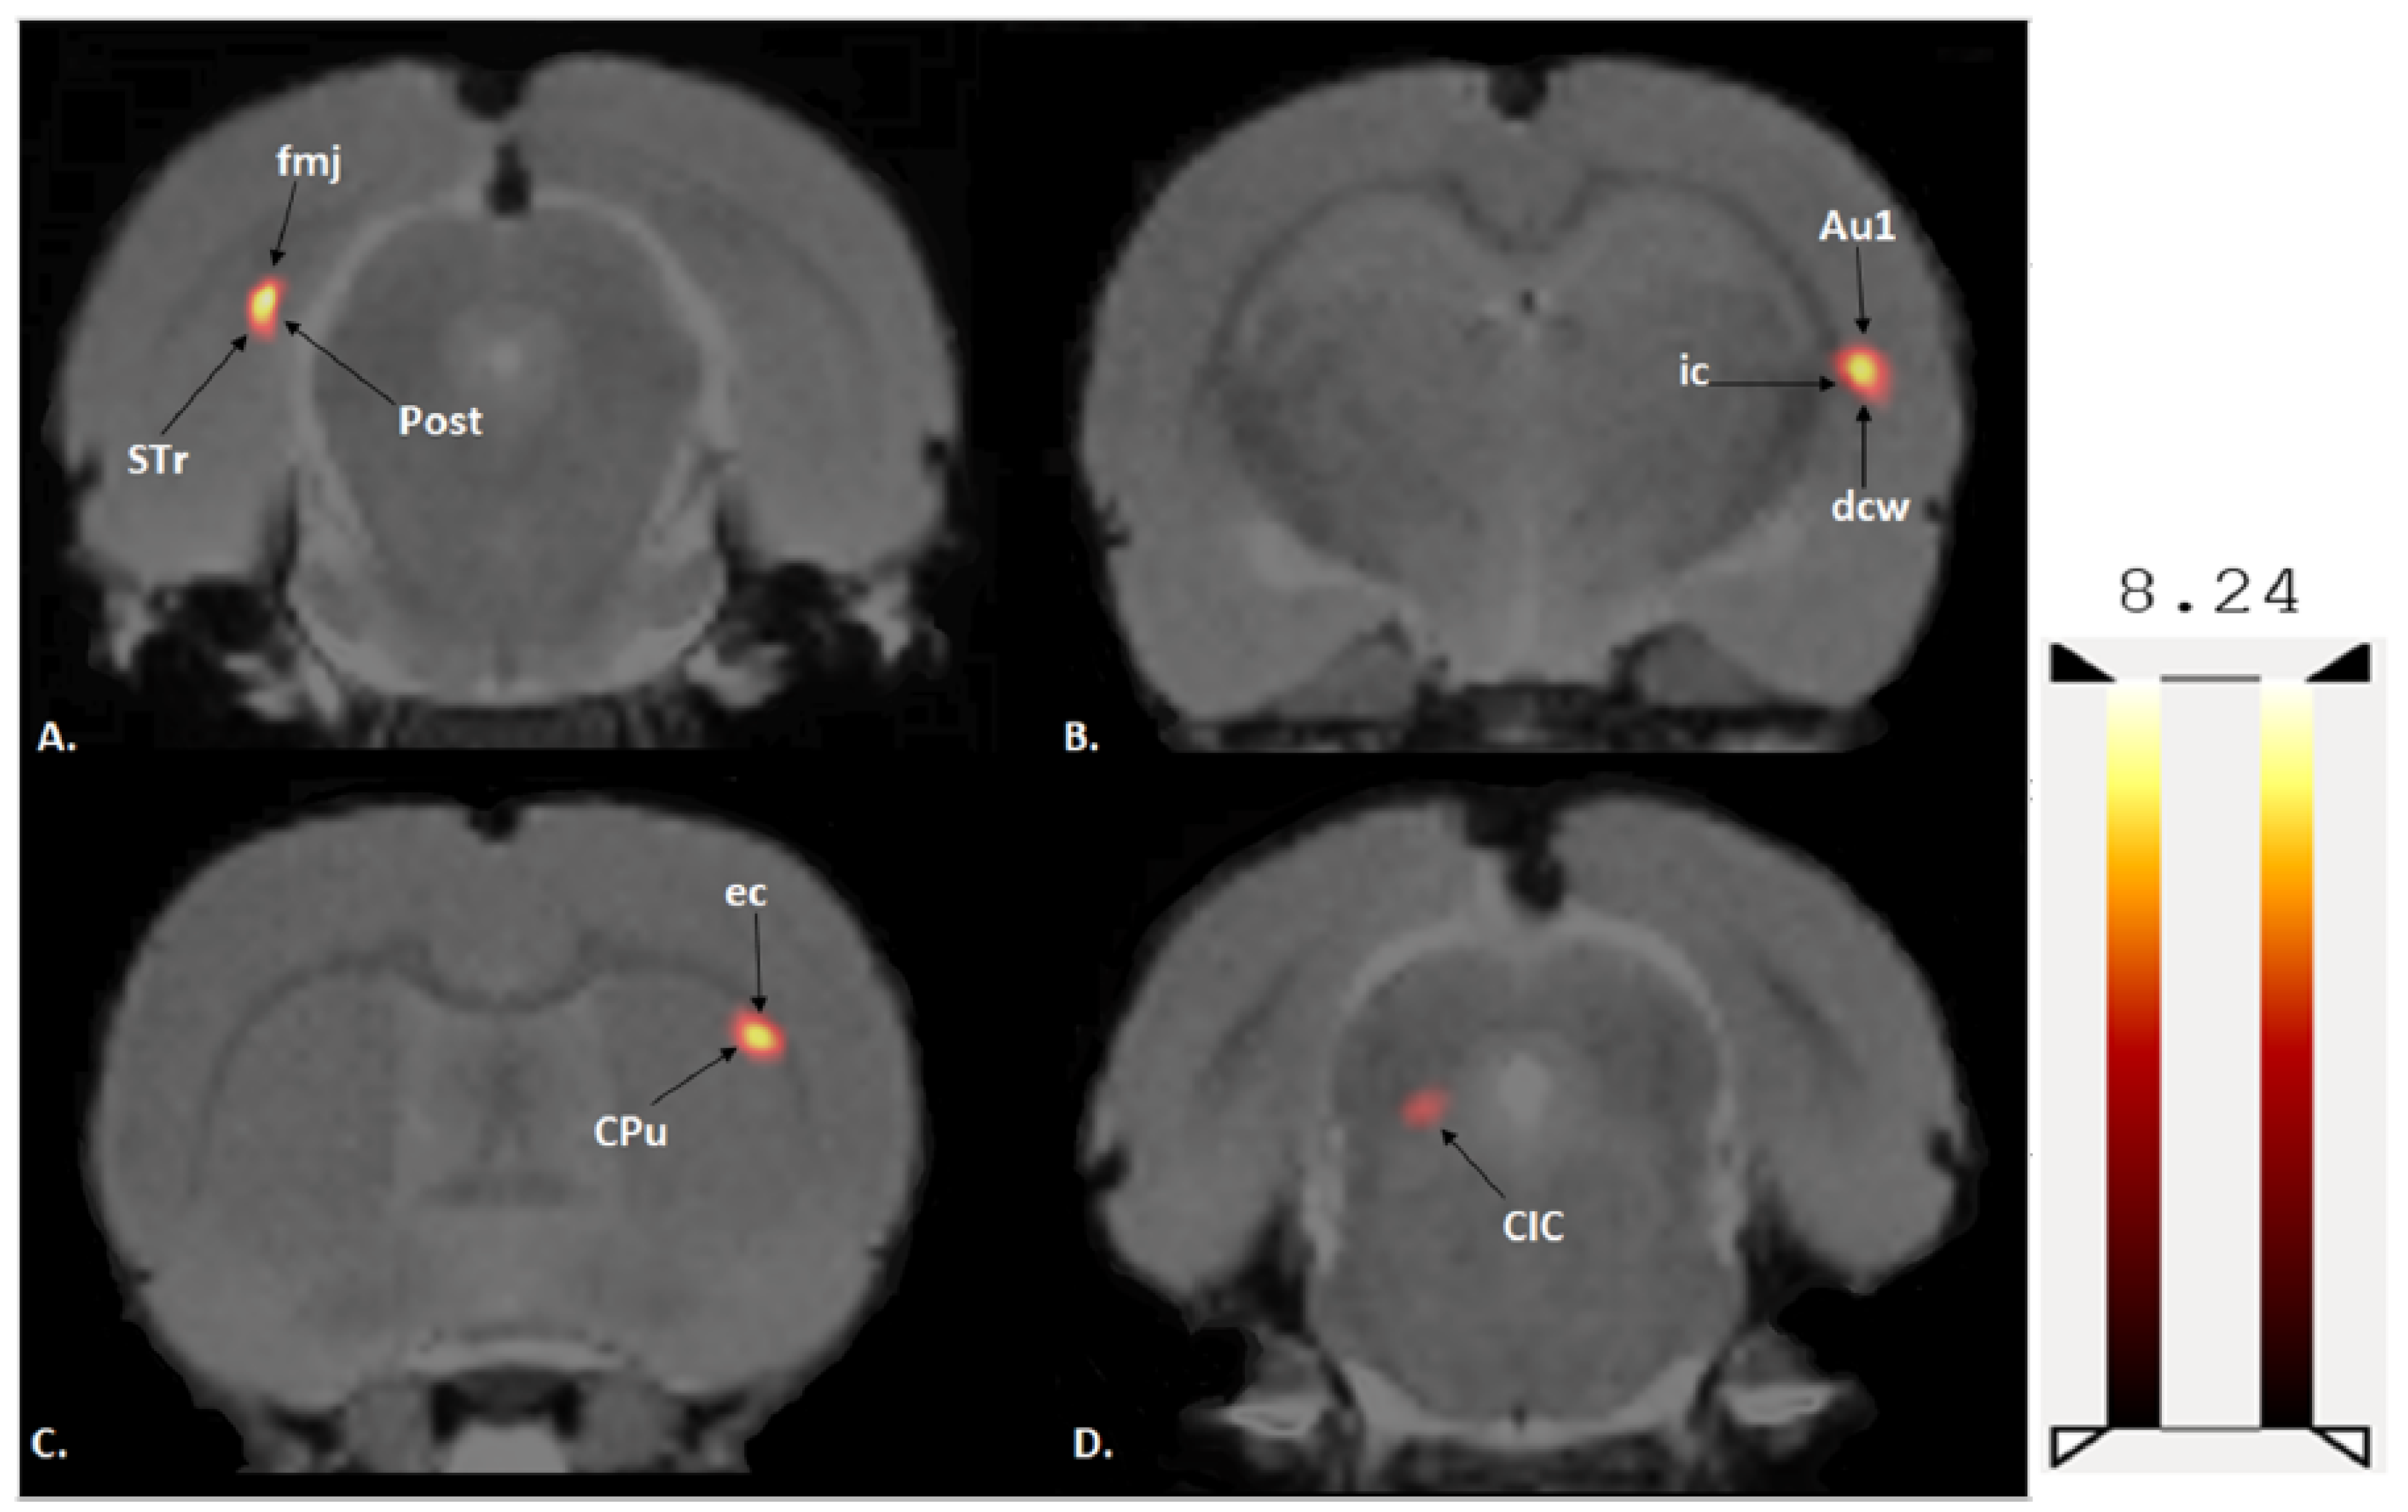

A two-sample t-test revealed that exercised rats showed significantly increased BGluM (p < 0.001 df = 11), K > 50) compared to sedentary rats in the following regions: caudate putamen (striatum) (CPu), external capsule (ec), internal capsule (ic), deep cerebellar white matter (dcw), primary auditory cortex (Au1), forceps major of the corpus callosum (fmj), postsubiculum (Post), subiculum transition area (STr), and the central nucleus of the inferior colliculus (CIC).

(Exercise > Sedentary; Table 1 and Figure 3) BGluM activation is mapped in the brain (p < 0.001, df = 11). Activated regions are indicated in the hot scale. There was no significant inhibition in BGluM observed in exercise rats when compared to the sedentary rats (p > 0.05).

Figure 3. Coronal PET images showing brain regions with significant (p < 0.001, df = 11, and K > 50) differences in brain glucose metabolism (BGluM) between exercised and sedentary rats. Hot scale clusters illustrate BGluM activation. The value 8.24 represents peak activation level, as expressed by the t-value: (A) fmj, Post, Subiculum, and STr; (B) ic, dcw, and Au1; (C) CPu and ec; and (D) CIC.